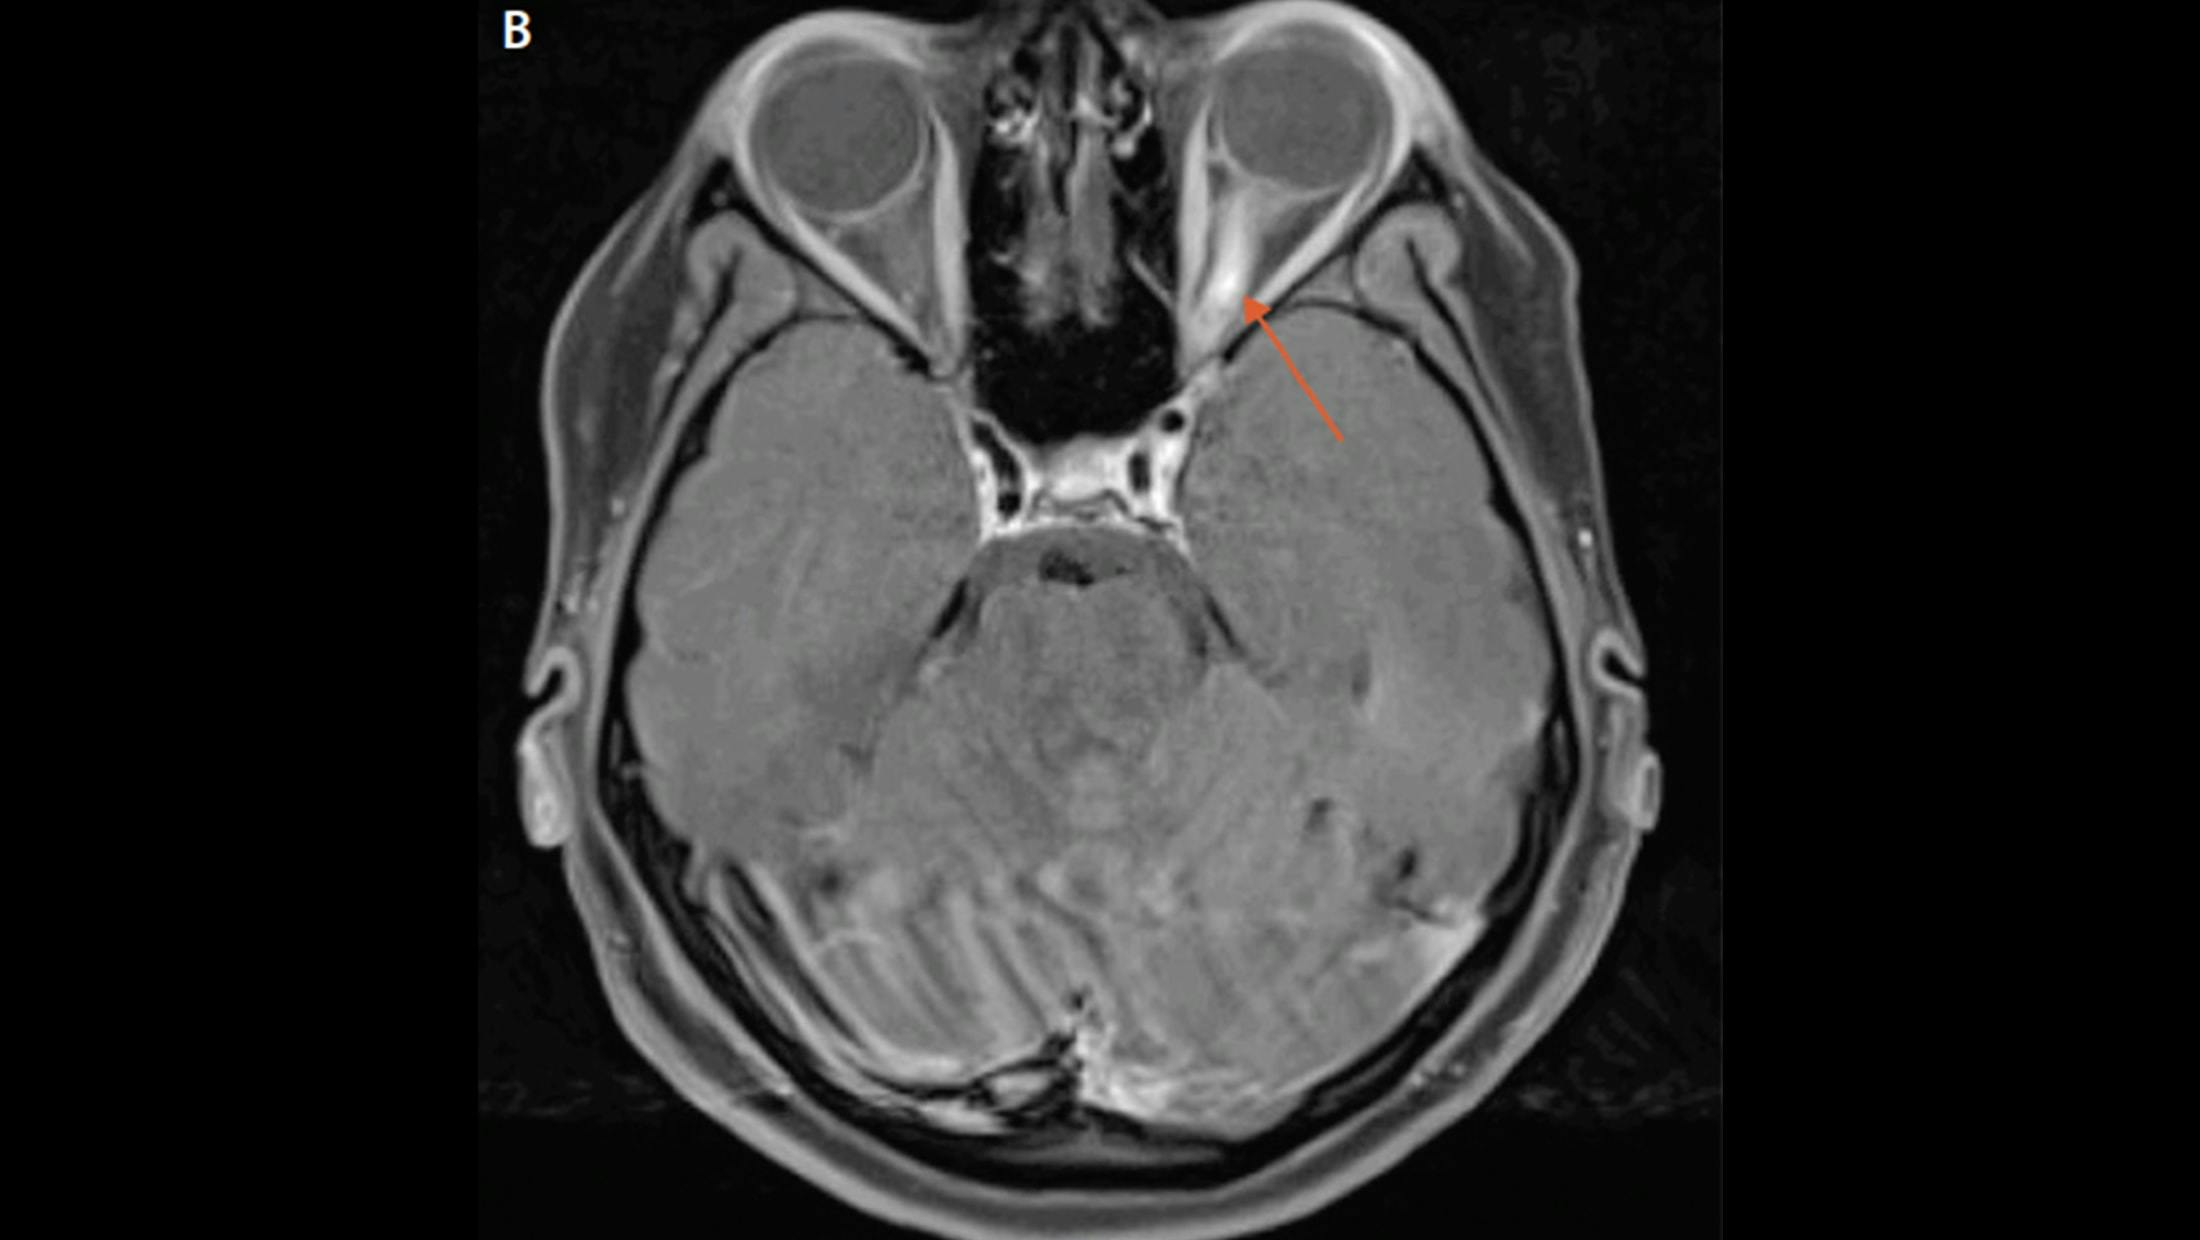

Longitudinally extensive enhancing optic nerve lesion in neuromyelitis optica spectrum disorder (NMOSD)

Brain MRI from Mr. L’s second hospitalization demonstrates resolution of the previously visualized right temporal lesion and leptomeningeal enhancement with new enhancing lesions both infra- and supratentorially bilateral optic neuritis with greater enhancement in the right optic nerve compared with the left.